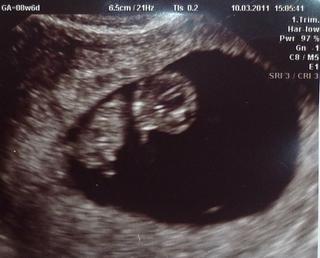

@masinka krásna fotka, gratulujem, dúfam že v stredu už aj ja budem mať konečne fotku 🙂